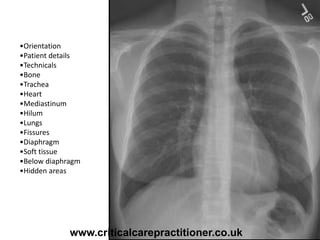

•Orientation

•Patient details

•Technicals

•Bone

•Trachea

•Heart

•Mediastinum

•Hilum

•Lungs

•Fissures

•Diaphragm

•Soft tissue

•Below diaphragm

•Hidden areas